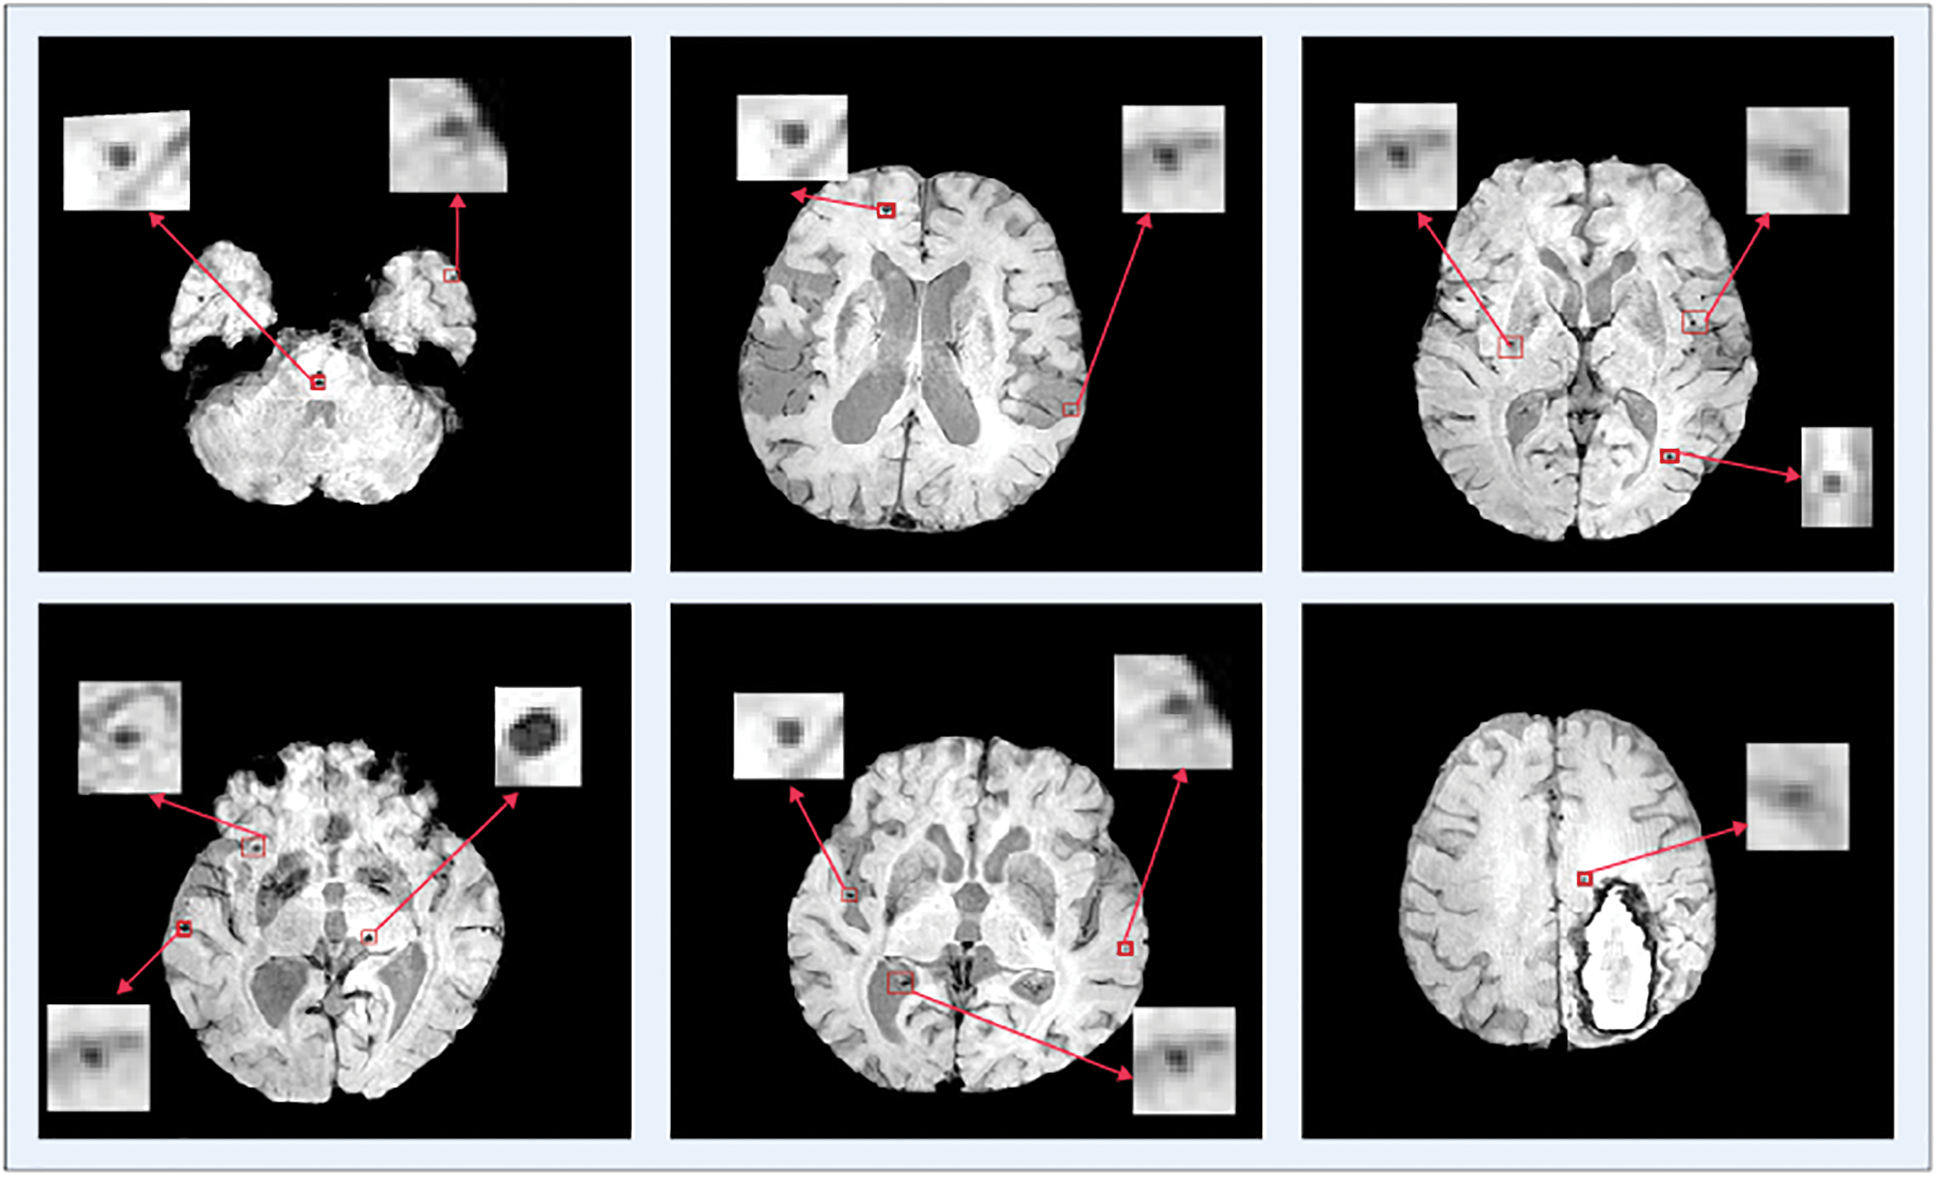

The data samples utilized in this proposed study are SWI dataset of a total of 20 individuals for the identification of Cerebral Micro Bleeds (CMB). These data samples are the same percentage of the great size data set utilized in [23]. Many data samples have more than one cerebral in it. Fig. 6 shows a few examples where a single MRI contains more than one CMB. These MRI data samples are produced from a Philips-medical scheme of 3.0T by set the reiteration 17 ms in time, 512 × 512 × 150 in volume size, the reverberation time of 24 ms, in-plane goals of 0.45 × 0.45 mm, and cut thickness of 2 mm and cut separating of 1 mm. The entire dataset is marked by two experienced raters by following a micro-drain functional rating-scale [24].

Figure 6: Single and multiple cerebral microbleeds in the brain MRI